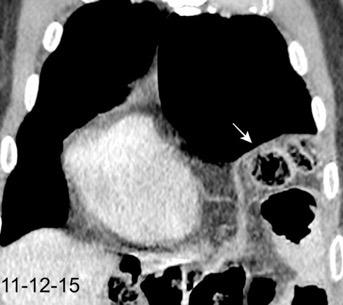

Parálisis frénica transitoria tras cirugía de válvula aórtica

Parálisis frénica transitoria post cirugía cardiaca (10%).

Puede acompañarse de atelectasia del LII.

Benjamin JJ et al. . Left lower lobe atelectasis and consolidation following cardiac surgery: the effect of topical cooling on the phrenic nerve. Radiology 1982